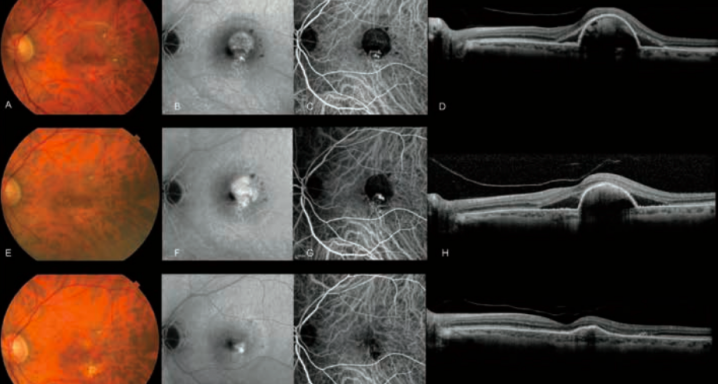

Las manifestaciones clínicas de la VCP actualmente son numerosas y las características más comunes demuestran que los pacientes sufren desprendimientos y hemorragias del epitelio pigmentario de la retina y que, en conjunto, puede venir derivado de la protrusión de unos vasos coroidales.

A todo esto, los fondos de ojo de los pacientes que sufren VCP pueden mostrar pocas drusas (depósitos localizados bajo la retina, compuestos por lípidos, y que aumentan el riesgo de desarrollar DMAE) y la angiografía con verde de indocianina es, en estos casos, la metodología que nos permite con rmar esta patología.

Ante esta situación poco habitual, el equipo del Dr. Jordi Monés decidió aplicar dos sesiones de Terapia Fotodinámica de Vertepor n (TFD) que se realizaron con un intervalo de 2 meses entre ambas sesiones. Además, se realizaron también dos inyecciones de ranibizumab 0,5 mg para conseguir una mejor regresión de la lesión polipoidal. Las 2 sesiones de TFD se espaciaron en solo 2 meses de diferencia.

Superado este plazo, y en la visita de seguimiento prevista con el paciente a partir del último tratamiento, la agudez visual del paciente era de 20/32 en el ojo derecho y aún presentaba tanto el desprendimiento del epitelio pigmentario del ojo izquierdo como el líquido subretiniano.

Como el tratamiento con láser térmico de las lesiones polipoidales no podía considerarse una opción de tratamiento a causa de su localización subfoveal, se exploraron las terapias alternativas. Por ello se decidió realizar de nuevo la angiografía con verde de indocianina.

Con esta nueva angiografía se identi có un vaso que nutría el complejo polipoidal de la circulación coroidal. El láser de diodo guiado por la angiografía con verde de indocianina se discutió previamente con el paciente y se llevó a cabo con una longitud de onda de 810 nm, una potencia de 300 mW, una duración de 0,2 milisegundos y con una medida del punto de 100 micras en los vasos nutrientes, que son los encargados de suministrar la circulación a las estructuras polipoideas. Todo ello se combinó con una inyección intravítrea 0,5 mg ranibizumab 2 días más tarde.

Con esta práctica, la oclusión de los vasos nutricios bloqueó el ujo sanguíneo de los pólipos y permitió, así, el aplanamiento del desprendimiento del epitelio pigmentario, la desaparición del líquido subretiniano, y la regresión de los pólipos solo 2 semanas después del tratamiento.

Ante esta práctica, innovadora en pacientes que no responden a los tratamientos habituales previstos para esta patología, las estructuras polipoidales del paciente, que estaban en regresión y con exudación subretiniana, se pudieron resolver y la agudez visual se conservó sin efectos adversos.